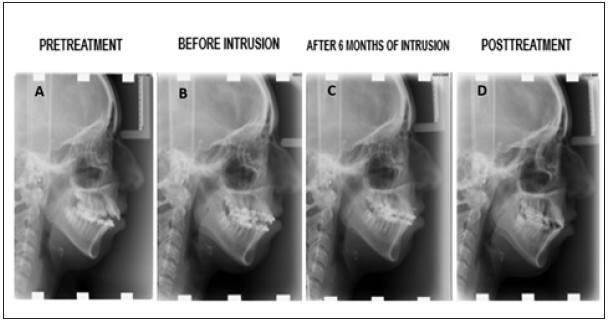

Figure 4:Lateral cephalograms. A, Pretreatment. B, Before Intrusion. C, After 6 Months of Intrusion.D, Posttreatment.

The post-treatment facial photographs showed that the patient was satisfied with the outcome of facial aesthetics. Macro esthetics and micro esthetics were achieved (Figure 7). Lip muscle activity was a little bit high and there was also an acceptable mental muscle hyperactivity. Normal overjet and overbite relationships were achieved. The skeletal class II relationship was corrected, mandibular autorotation was obtained, leveling and alignment was achieved, and a balanced occlusion was obtained (Figure 8). Open bite was corrected, normal incisal relationship and normal canine guidance were obtained. The outcome of posttreatment panoramic graph displayed an acceptable root parallelism (Figure 9). No sign of root resorption was evident. Retention was done both by canine to canine bonded fixed retainer and a vacuum formed retainer (VFR). Facial, dental esthetics, and dental stability mostly maintained during the 5-year retention period (Figure 4 & 10). There are some changes in occlusion (mild relapse) but patient remained without any symptom during the post-treatment period.

Because of overgrowth the posterior dentoalveolar region in the maxilla and mandible; anterior open bite can occur [19]. Previous studies displayed that molar intrusion by TADs was an efficient treatment choice in patients with anterior open bite and gummy smile providing molar intrusion, counterclockwise rotation of the mandible, and correction of open bite without incisal elongation; hence, this option was chosen for treating the patient to correct the anterior open bite and to reduce the appearance of gummy smile via using miniscrew anchorage [20,21]. According to the study which was done by Xun et al. [22] showed that miniscrews can intrude both maxillary and mandibular molars by an average of 1.8mm and 1.2mm. This measurement can lead to a counterclockwise rotation of the mandible. In this case, maxillary molars were intruded by 1.7mm and FMA decreased by 1.2°. It was showed that the mandibular plane angle was reduced by 4.6°, which provide a counterclockwise rotation of the mandible with a decrease in the anterior facial height. In this case report, upper molar intrusion was necessary for the counterclockwise rotation of the mandible and effecting the appearance of gummy smile. Therefore, a treatment plan was chosen to intrude the upper molars and to prevent elongation of upper incisors using miniscrews. Localization of miniscrews depends on the required force for orthodontic treatment. In the maxilla most preferred region for miniscrew insertion is buccal alveolar bone between the molars or palatal region [3,11]. The palatal region is preferred for insertion of miniscrews in intrusion cases; because of containing lack of nerves and blood vessels and the distance to the molars is longer than buccal alveolar bone [11]. Both buccal and palatal miniscrews were used to obtain a force which is close to direct intrusion force. For an absolute intrusion of molars, the force should be applied from both direction (buccal and palatal direction [9,11]. In this case, intrusion of molars and inhibition of incisors elongation were achieved by miniscrews. Because of requiring minimal cooperation and achieving maximum anchorage for treatment make miniscrews most preferred treatment option [23,24]. Subtelny & Sakuda [25] mentioned at their study that if patient has a real skeletal open bite, treating the patient with conventional orthodontics is impossible [25].